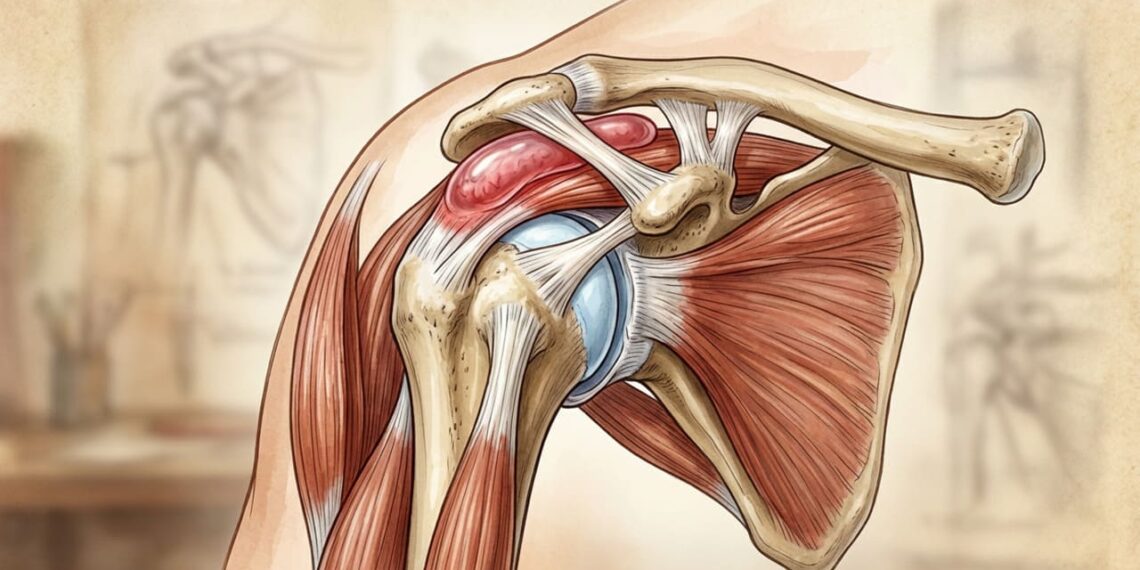

A bursite no ombro é a inflamação da bursa, uma pequena bolsa cheia de líquido que amortece o atrito entre os ossos, tendões e músculos da articulação. Quando essa estrutura se irrita, surgem dores ao levantar o braço, dificuldade em realizar tarefas simples e limitação dos movimentos. Entender as causas, saber diferenciar de outras lesões e conhecer os tratamentos disponíveis é fundamental para evitar que o quadro se torne crônico e prejudique a rotina.

O que é a bursa e por que ela inflama?

A bursa funciona como um pequeno amortecedor natural, reduzindo o atrito entre os tendões e os ossos do ombro durante o movimento. Quando há excesso de esforço ou atrito repetitivo, esse tecido incha e gera dor.

As causas mais comuns incluem movimentos repetitivos com os braços acima da cabeça, má postura, traumas diretos e envelhecimento natural das articulações, fatores que levam ao acúmulo de líquido inflamatório.

Embora causem sintomas parecidos, bursite e tendinite atingem estruturas diferentes. A bursite afeta a bolsa que amortece a articulação, enquanto a tendinite envolve a inflamação dos tendões que conectam músculos aos ossos.

Em muitos casos, as duas condições aparecem juntas, já que o atrito entre tendões irritados e a bursa pode desencadear um ciclo inflamatório. Por isso, o diagnóstico preciso é essencial para direcionar o tratamento correto.